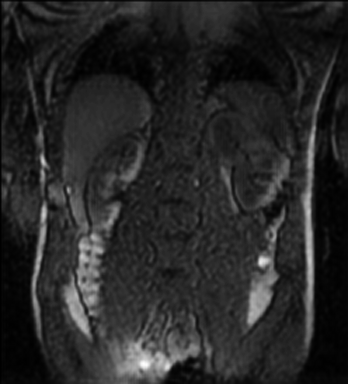

Tables 1 and 2 show our quantitative results: PSNR between the style (image we want to transfer style from) and generated image, SSIM and MS-SSIM between the content (image we want to take structure from) and generated image and finally, our proposed weighted SSIMs. For each style transfer direction and metric, our method consistently outperforms the other approaches. Figures 2 and 3 qualitatively highlight the good results of our method on 2D and 3D datasets. In addition, quantitative results on both figures show that our proposed metric preserves qualitative ordering of results for both style and content. In comparison, metrics such as SSIM struggle to accurately correlate to visual results.

Qualitative evaluation shows that the proposed method leads to sharper images, better content preservation, better localised CE and realistic MRI appearance. Quantitatively, we outperform the other algorithms with each metric, for each style transfer direction. While we expected that adding CE to images would be an easier task than removing CE, we found that for both tasks the method exhibits similarly performing quantitative and qualitative results. The results for style transfer with the kidney data show that when there is clear CE, it is easier to perform style transfer in both directions. However, when style transfer is performed on the prostate data, the model struggles in comparison to the kidney data. This may be due to the enhancement of the prostate being less defined than the kidney data. In figure 3(b), we can see the prostate with CE. Compared to figure 2(b) showing kidneys with CE, it is harder to determine the edges. The two original images shown in figures 3(a) and 3(b) are clear and easy to see some edges of prostate, in other images, it is harder to see the edges of the prostate.

(C) CW-SSIM: 0.93

(S) CW-SSIM: 0.73